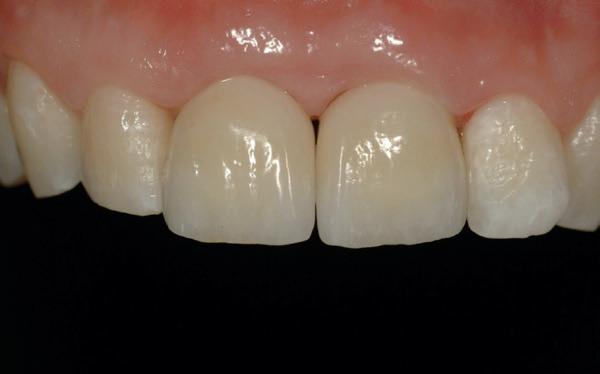

13. Techniekmodel

plaatsing van de restauraties werden zowel de tandboog als de tandstand in de bovenkaak gecorrigeerd (afbeelding 13-15).

Aansluitend werd de onderkaak volgens hetzelfde principe gerehabiliteerd, resulterend in een stabiele, functionele en esthetisch gebalanceerde occlusie (afbeelding 16-17).